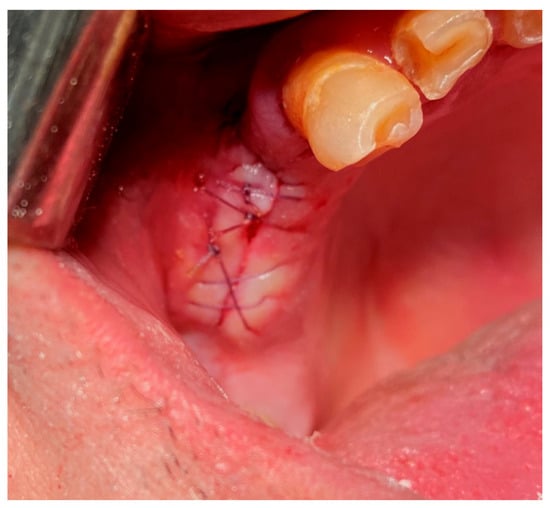

Similar to the horizontal mattress suture, this technique includes locking stitches to secure the wound edges more effectively [48,49]. Once placed, sutures are secured by tying knots manually using surgical instruments, as shown in Figure 9 [59,60].

Figure 9. Horizontal mattress locking suture. Reprinted with permission from Ref. [61]. Copyright 2024 Lax Book: Plovdiv.